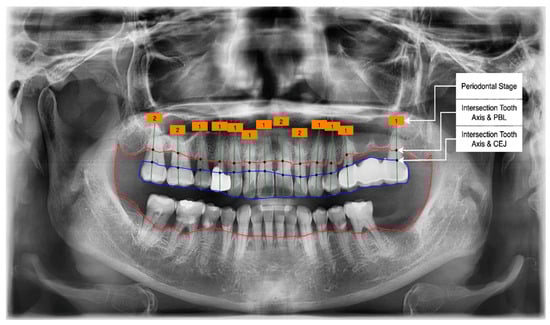

- Get the intersection of the PBL’s upper side and the tooth’s middle axis.

- Get the intersection of the CEJ’s upper side and the tooth’s middle axis.

- Calculate the length from those two intersections (known as the RBL length).

- Calculate the RBL percentage from the RBL length and tooth root.

Classification of the PBL by Percentage Rate Analysis